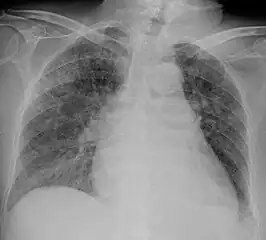

Chest X ray showing miliary tuberculosis

Miliary tuberculosis is a form of tuberculosis that is characterized by a wide dissemination into the human body and by the tiny size of the lesions (1–5 mm). Its name comes from a distinctive pattern seen on a chest radiograph of many tiny spots distributed throughout the lung fields with the appearance similar to millet seeds—thus the term "miliary" tuberculosis. Miliary TB may infect any number of organs, including the lungs, liver, and spleen.[2] Miliary tuberculosis is present in about 2% of all reported cases of tuberculosis and accounts for up to 20% of all extra-pulmonary tuberculosis cases.[3]

Testing for miliary tuberculosis is conducted in a similar manner as for other forms of tuberculosis, although a number of tests must be conducted on a patient to confirm diagnosis.[4] Tests include chest x-ray, sputum culture, bronchoscopy, open lung biopsy, head CT/MRI, blood cultures, fundoscopy, and electrocardiography.[10] The tuberculosis (TB) blood test, also called an Interferon Gamma Release Assay or IGRA, is a way to diagnose latent TB. A variety of neurological complications have been noted in miliary tuberculosis patients—tuberculous meningitis and cerebral tuberculomas being the most frequent. However, a majority of patients improve following antituberculous treatment. Rarely lymphangitic spread of lung cancer could mimic miliary pattern of tuberculosis on regular chest X-ray. [15]